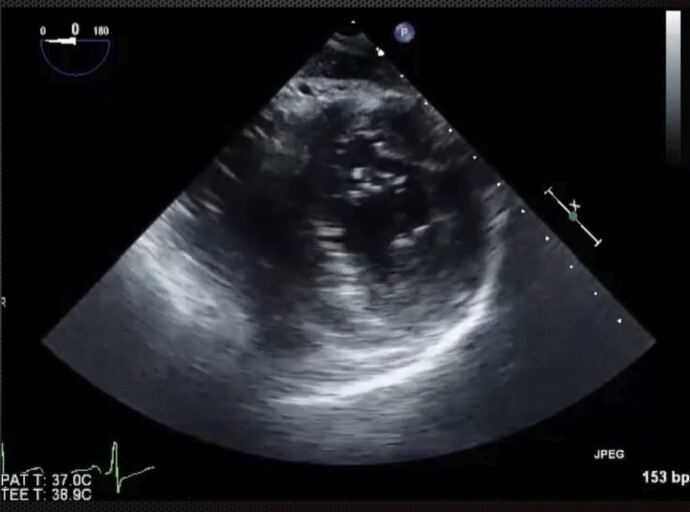

Trans-gastric mid-papillary short axis view - start at ME 4CH view at 0 on the multiplane, advance probe to stomach and then anteflex. Manipulate probe depth until you can see posteromedial and anterolateral papillary muscles. See right and left ventricles. Good for regional wall movement abnormalities. Good for volume assessment.